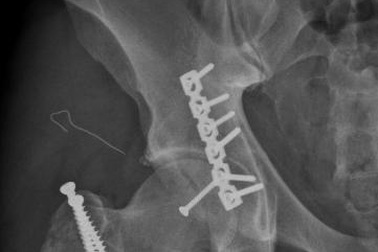

Điều trị thành công cho người đàn ông trật khớp háng nhân tạo 2 lần, tưởng chừng tàn phếĐội ngũ bác sĩ khoa Chấn thương chỉnh hình tại Bệnh viện Đa khoa Quốc tế Nam Sài Gòn đã giúp người đàn ông 65 tuổi từng đối mặt với biến chứng trật khớp háng sau 2 cuộc phẫu thuật thất bại phục hồi lại khả năng đi lại.